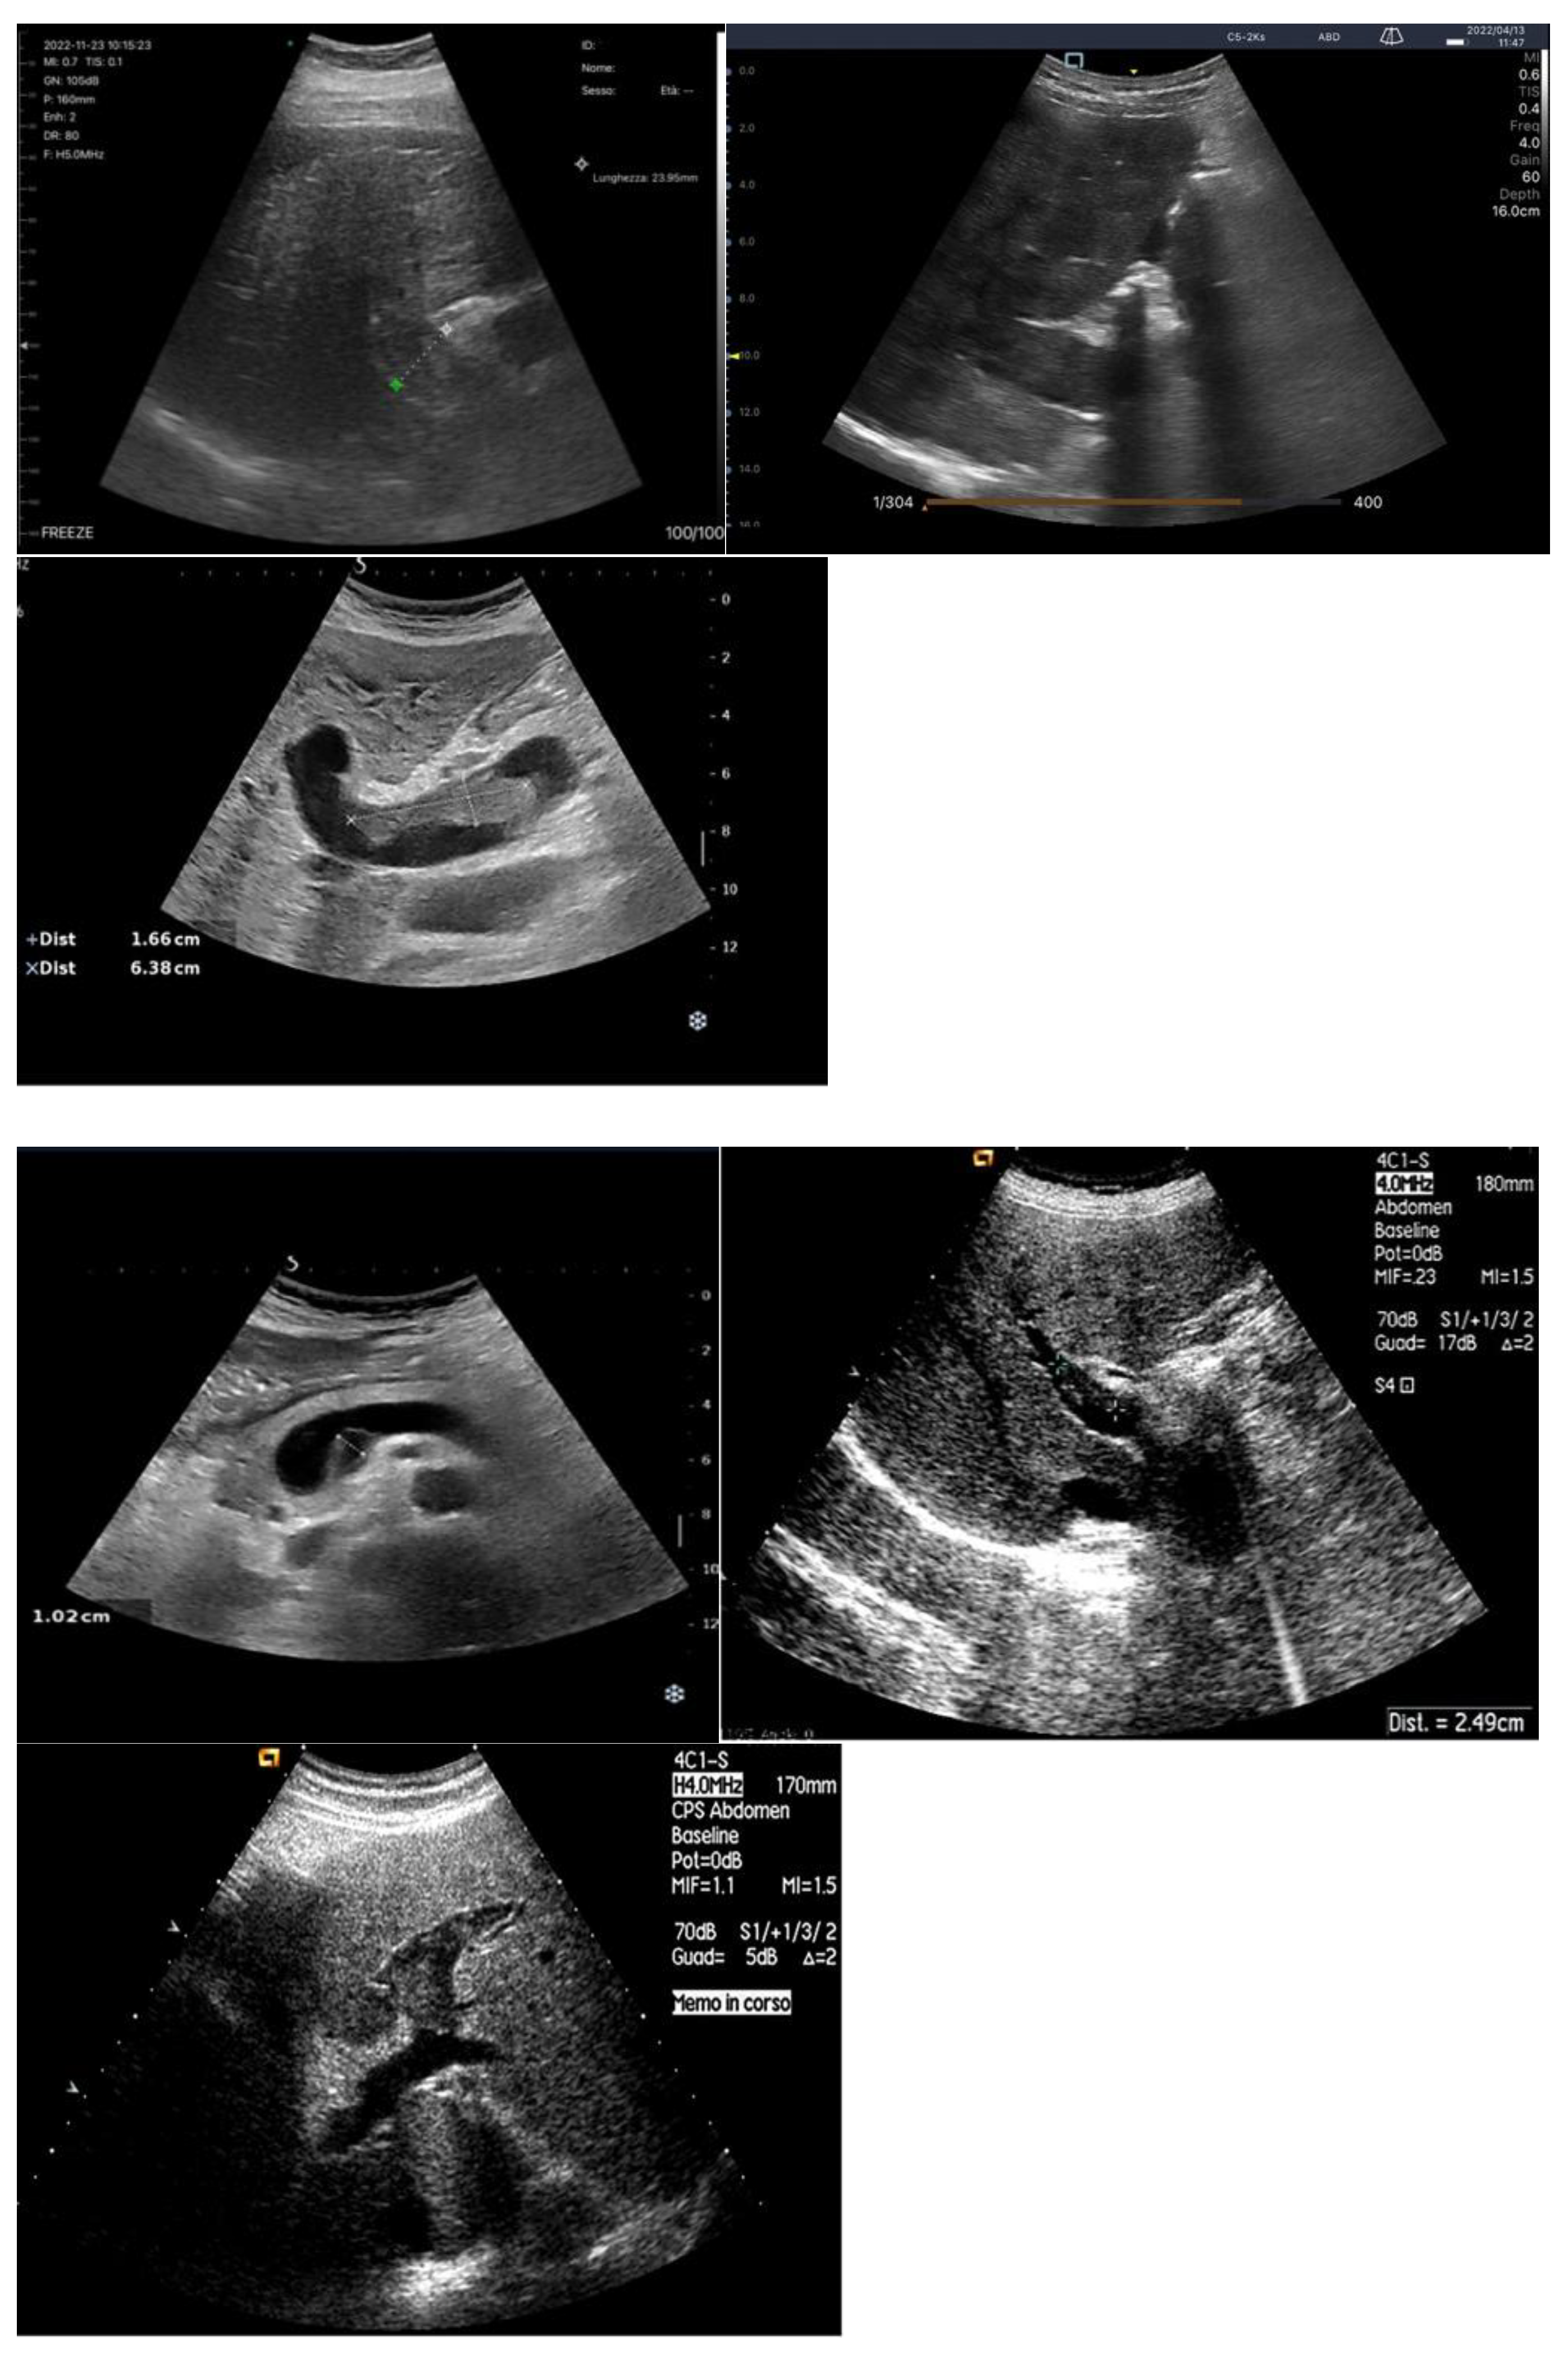

Bowel-Wall Thickening

Venous Congestion

- Ikeda, Y.; Ishii, S.; Fujita, T.; Iida, Y.; Kaida, T.; Nabeta, T.; Maekawa, E.; Yanagisawa, T.; Koitabashi, T.; Takeuchi, I.; et al. Prognostic impact of intestinal wall thickening in hospitalized patients with heart failure. International journal of cardiology 2017, 230, 120-126. [CrossRef]

- Ikeda, Y.; Ishii, S.; Maemura, K.; Oki, T.; Yazaki, M.; Fujita, T.; Nabeta, T.; Maekawa, E.; Koitabashi, T.; Ako, J. Association between intestinal oedema and oral loop diuretic resistance in hospitalized patients with acute heart failure. ESC Heart Fail 2021, 8, 4067-4076. [CrossRef]

- Hao, R.; Zheng, Y.; Zhao, Q.; Chen, J.; Fan, R.; Chen, P.; Yin, N.; Qin, H. Evaluation value of ultrasound on gastrointestinal function in patients with acute heart failure. Front Cardiovasc Med 2024, 11, 1475920. [CrossRef]

- Ikeda, Y.; Ishii, S.; Yazaki, M.; Fujita, T.; Iida, Y.; Kaida, T.; Nabeta, T.; Nakatani, E.; Maekawa, E.; Yanagisawa, T.; et al. Portal congestion and intestinal edema in hospitalized patients with heart failure. Heart and vessels 2018, 33, 740-751. [CrossRef]